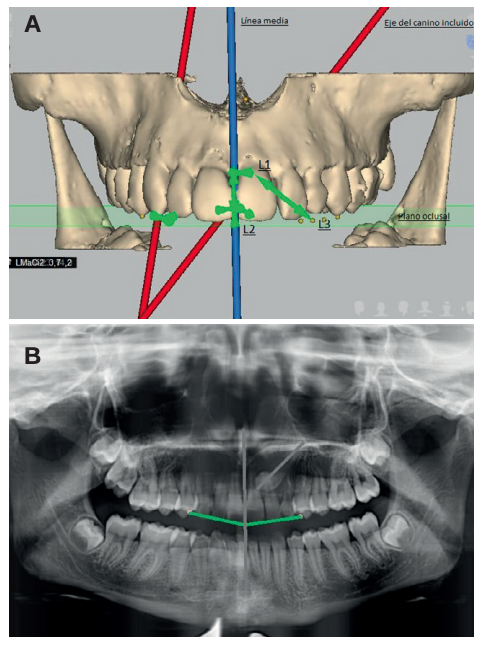

Diagnóstico radiográfico de los caninos maxilares incluidos. Comparación entre dos y tres dimensiones

Introducción: La inclusión de caninos tiene una alta incidencia y plantea varias complicaciones clínicas, siendo de vital importancia el diagnóstico precoz y exacto para minimizar los riesgos y complicaciones derivadas. El objetivo de este trabajo es analizar, utilizando como referencia las líneas planteadas por Alqerban, la efectividad de las dos dimensiones en el diagnóstico volumétrico de la inclusión de los caninos maxilares.

Métodos: Seleccionamos 27 pacientes con 36 caninos maxilares incluidos que se realizaron estudio de ortodoncia con ortopantomografía y tomografía computarizada de haz cónico (Cone Beam Computed Tomography, CBCT) del maxilar en la Clínica Universitaria de la Universidad Europea. Se trazaron tres líneas de referencia basándose en la distancia de la cúspide del canino al plano oclusal (L1), a la línea media (L2) y a su lugar ideal de erupción (L3), tanto en la ortopantomografía como en el CBCT. Como valores de referencia ideales seleccionamos un grupo control de 36 caninos maxilares erupcionados.

Resultados: Se compararon los resultados en dos y tres dimensiones mediante la prueba T de Student, tras comprobar su distribución normal mediante la prueba de contraste de Anderson-Darling. No se obtuvo significación estadística (p>0.05) para ninguna de las variables estudiadas.

Conclusiones: El uso del CBCT es vital para asegurar un buen diagnóstico en cuanto a la posición del canino y su relación con estructuras adyacentes y así establecer un plan de tratamiento adecuado. Aun así, la ortopantomografía aporta información suficiente para la planificación inicial.

Radiographic diagnosis of impacted maxillary canines: Comparison between two and three dimensions

Introduction: An impacted canine is a very common condition and raises several clinical complications. Early and exact diagnosis is important in order to minimise the risks and subsequent complications. The objective of this study is to analyse the effectiveness of two dimensions in the volumetric diagnosis for impacted maxillary canines, using the lines proposed by Alqerban as a reference.

Methods: An orthodontic study of the maxilla using orthopantomography with cone beam computed tomography (CBCT) at the Madrid European University Clinic was performed on 27 patients selected with 36 maxillary impacted canines. Three reference lines were drawn based on the distance from the cusp of the canine to the occlusal plane (L1), to the midline (L2) and to its ideal eruption site (L3), in both the orthopanthomography and the CBCT. As ideal reference values, we selected a control group of 36 erupted maxillary canines.

Results: The results were compared in 2 and 3 dimensions using the Student’s t test, after verifying their normal distribution using the Anderson-Darling contrast test. Statistical significance (p > 0.05) was not obtained for any of the variables studied.

Conclusions: The use of CBCT is vital to ensure good diagnosis of the canine position and its relationship with adjacent structures and thus establish an adequate treatment plan. However, orthopantomography provides sufficient information for initial planning.